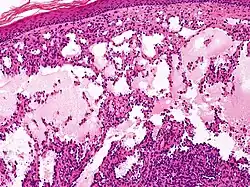

Cavernous lymphangioma, H&E stain. Irregular, dilated spaces are visible in dermis.

Lymphangiomas have traditionally been classified into three subtypes: capillary and cavernous lymphangiomas and cystic hygroma. This classification is based on their microscopic characteristics. A fourth subtype, the hemangiolymphangioma is also recognized.[12]

Cavernous lymphangiomas

Composed of dilated lymphatic channels, cavernous lymphangiomas characteristically invade surrounding tissues.

Microscopically, the vesicles in lymphangioma circumscriptum are greatly dilated lymph channels that cause the papillary dermis to expand. They may be associated with acanthosis and hyperkeratosis. There are many channels in the upper dermis which often extend to the subcutis (the deeper layer of the dermis, containing mostly fat and connective tissue). The deeper vessels have large calibers with thick walls which contain smooth muscle. The lumen is filled with lymphatic fluid, but often contains red blood cells, lymphocytes, macrophages, and neutrophils. The channels are lined with flat endothelial cells. The interstitium has many lymphoid cells and shows evidence of fibroplasia (the formation of fibrous tissue). Nodules (A small mass of tissue or aggregation of cells) in cavernous lymphangioma are large, irregular channels in the reticular dermis and subcutaneous tissue that are lined by a single layer of endothelial cells. Also an incomplete layer of smooth muscle also lines the walls of these channels. The stroma consists of loose connective tissue with a lot of inflammatory cells. These tumors usually penetrate muscle. Cystic hygroma is indistinguishable from cavernous lymphangiomas on histology.[7]